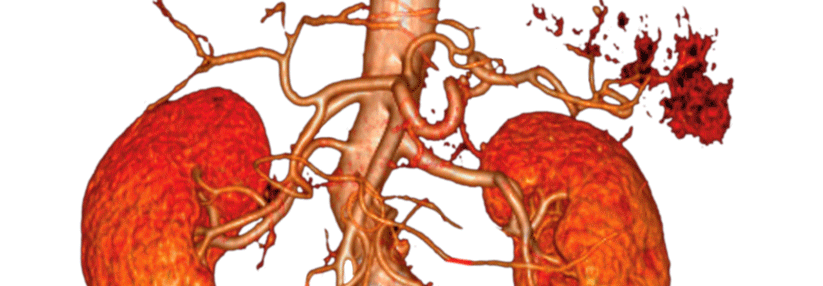

Auch hinsichtlich Letalität zogen Patientinnen den Kürzeren: Zwar ähnelten sich die Zehn-Jahres-Überlebensraten beim klassischen Vorgehen, nach dem endovaskulären Eingriff lagen sie bei Frauen jedoch deutlich niedriger (23 % vs. 37 %). Die höhere Sterberate bei Frauen ging, wie die Mediziner bei der weiteren Analyse herausfanden, vor allem auf die höhere Sterblichkeit nach elektiver endovaskulärer Ausschaltung und nach offenen Notfalleingriffen bei Rupturen zurück.

Da der Trend insgesamt Richtung endovaskulärer Aortenreparatur geht, sind die beobachteten Geschlechterunterschiede bei diesem Verfahren bedenklich, so die Autoren. Über die Ursachen der Differenzen könne man derzeit nur spekulieren. Möglicherweise existieren für Frauen einfach keine passenden Stentgrafts, da sich ihre Befunde anatomisch oft komplexer präsentieren – z.B. mit einem kürzeren und schmaleren Aneurysmahals.